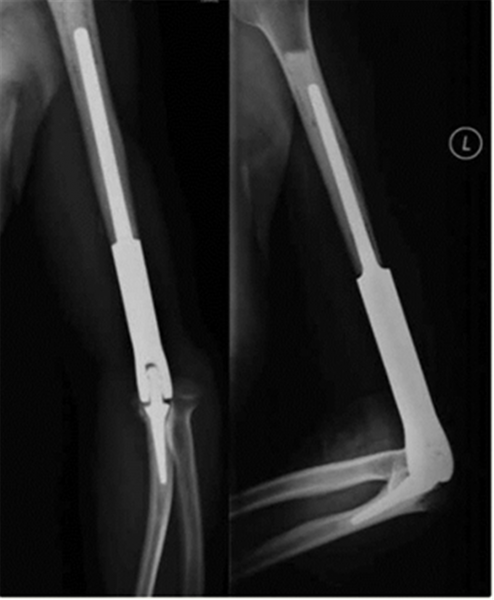

全肘关节假体,切除范围大,术后旋转功能差,容易出现骨折等并发症。

术前规划。

经过精准术前测量,烟台山医院与上海交通大学医学3D打印创新研究中心的工程师及专家进行反复沟通,个性化定制出完全符合该患者自身尺寸及规格的假体,制定打印出来匹配的截骨导板。手术过程十分顺利,术后患者功能恢复良好。